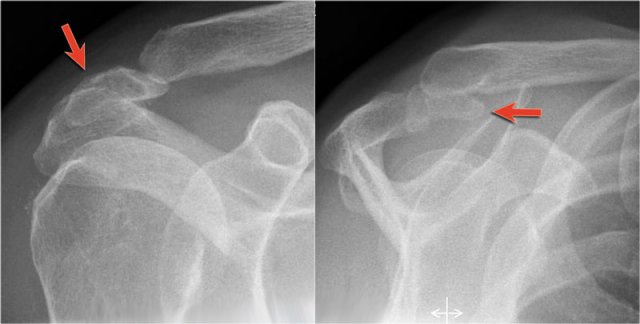

Os Acromiale

Failure of one of the acromial ossification centers to fuse will result in an os acromiale.

It is present in 5% of the population.

Usually it is an incidental finding and regarded as a normal variant.

The os acromiale may cause impingement because if it is unstable, it may be pulled inferiorly during abduction by the deltoid, which attaches here.

On MR an os acromiale is best seen on the superior axial images.

An os acromiale must be mentioned in the report, because in patients who are considered for subacromial decompression, the removal of the acromion distal to the synchondrosis may further destabilize the synchondrosis and allow for even greater mobility of the os acromiale after surgery and worsening of the impingement (4).

The axial MR-images show an os acromiale with degenerative changes, i.e. subchondral cysts and osteophytes (arrow).